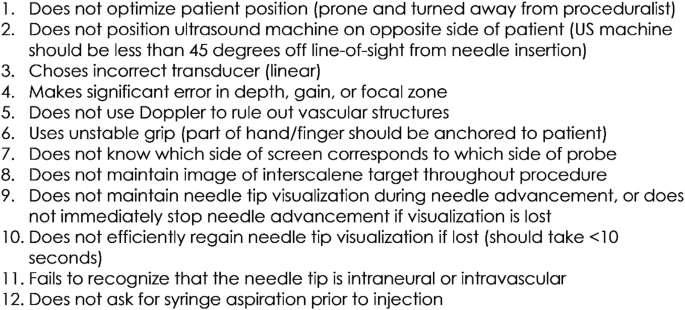

Needle placement assessment: Using an interscalene nerve block trainer with simulated neck anatomy, residents were graded on their ability to guide a needle using in-plane technique into proper position under ultrasound guidance. Scoring was based upon the validated Modified Cheung Checklist (Fig. 3) [24, 25]. Passage was defined as successful placement of the needle at the target site and the presence of fewer than 5 “quality compromising behaviors.”

Fig. 3

(adapted from Wong et al. [25])

Needle placement scoring metric. Passage of this assessment required identification of the needle tip in the interscalene groove along with the presence of 4 or fewer of the following behaviors

During the needle placement assessments, there were no intraneural or intravascular injections, and all participants ultimately placed the needle tip at the intended target. In the immediate post-workshop assessment, no resident lost more than 2 points. The most-missed points were for failure to use Doppler and failure to aspirate prior to injecting (27% and 17% of participants, respectively). Three months post-workshop, 2 participants lost 3 points and the remainder lost 2 or fewer. The most-missed points were for failure to use Doppler and failure to always maintain needle tip visualization during needle advancement (34% and 24% of participants, respectively).